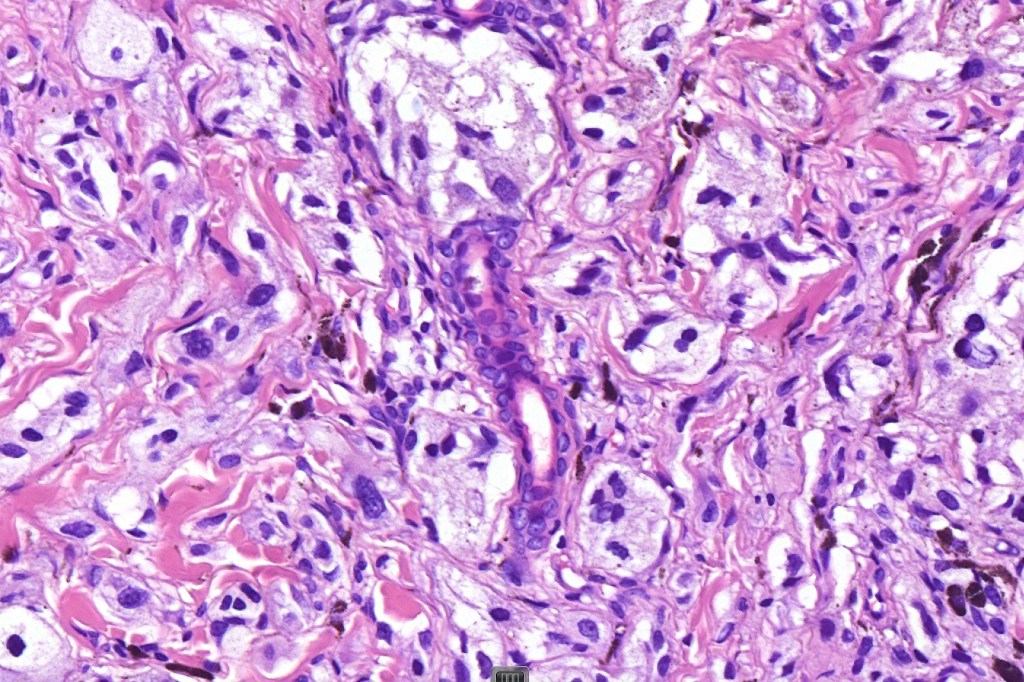

•Focal atypia (enlarged, hyperchromatic nuclei)

•Clear cells

•Multinucleate giant cells

• Cytoplasmic intranuclear pseudo-inclusions, small eosinophilic nucleoli

Atypical features which may be encountered include marked nuclear pleomorphism, conspicuous mitotic activity, atypical mitoses (atypical or borderline lesion)- may be associated with lymph node involvement although frank maliganncy is exceptional